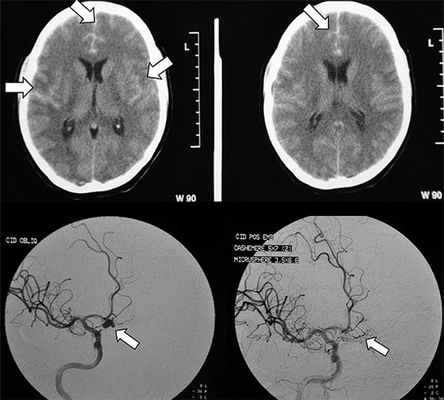

Сосудистый спазм, возникающий при субарахноидальном кровоизлиянии, является неблагоприятным фактором течения заболевания, а также обусловливает развитие вторичных ишемических осложнений головного мозга. Ранняя и адекватная диагностика вазоспазма позволяет прогнозировать тяжесть заболевания и выбрать наиболее рациональную тактику лечения. Цель: оценка диагностической эффективности селективной церебральной ангиографии у больных с сосудистым спазмом на фоне субарахноидального кровоизлияния Материал и методы. Обследовано 147 больных с субарахноидальным кровоизлиянием различной этиологии. Диагностический спектр исследования состоял из КТ головного мозга, электроэнцефалографии, транскраниальной допплерографии и тотальной селективной церебральной ангиографии. Результаты. Спазм сосудов головного мозга выявлен у 122 (82,9%) больных. Сосудистый спазм I типа диагностирован у 26 (21,3%) больных, II типа – у 34 (27,9%), III типа – у 40 (32,8%), IV типа – у 22 (18%). При сравнительном анализе данных ангиографии и транскраниальной допплерографии умеренному сосудистому спазму соответствовала линейная скорость кровотока (ЛСК) в средней мозговой артерии 120–150 см/с при полушарном индексе (ПИК) больше 4, что мы наблюдали у 52 (42,6%) больных. Выраженный сосудистый спазм – ЛСК 150–200 см/с при ПИК больше 5 наблюдался у 65 (53,3%) пациентов, критический сосудистый спазм с ЛСК более 200 см/с при ПИК больше 6 – у 5 (4,1%) пациентов. Выводы. Селективная ангиография сосудов головного мозга является высокоэффективным и относительно безопасным диагностическим методом исследования у больных с сосудистым спазмом. Ранняя диагностика сосудистого спазма путем проведения транскраниальной допплерографии и церебральной ангиографии позволяет прогнозировать тяжесть течения субарахноидального кровоизлияния и вторичных ишемических осложнений.

В классификации Фишера вид кровоизлияния оценивается по данным компьютерной томографии, в ней выделяется четыре группы:

- I группа – КТ не показывает наличие кровив субарахноидальном пространстве,

- II – диффузное кровоизлияние или сгустки крови в субарахноидальном пространстве толщиной до 1 мм,

- III – сгустки крови в субарахноидальном пространстве толщиной более 1 мм,

- IV – сгустки крови в субарахноидальном пространстве в сочетании с внутрижелудочковым или внутримозговым кровоизлиянием.